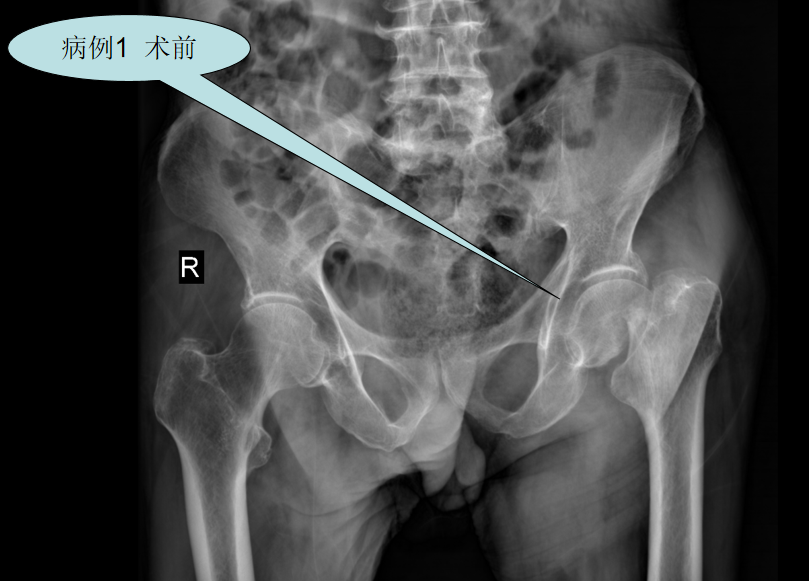

【病例一】